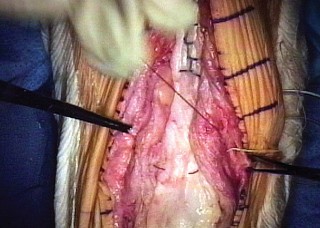

The most critical step of the procedure is the proximal tensioning of the graft. The knee must be placed in full, rigid extension. The allograft quadriceps tendon is draped over the host quadriceps tendon.

The reconstruction must be tensioned maximally. A common technical error is under-tensioning the graft, which inevitably leads to a profound postoperative extensor lag. Heavy, non-absorbable sutures (such as #5 or #2 ultra-high-molecular-weight polyethylene) are used to weave the allograft and host quadriceps tendons together using a Krackow or similar locking stitch technique. The graft should be tensioned such that the reconstructed patella sits at the appropriate joint line level, avoiding patella baja or alta.

If a synthetic mesh is utilized instead of an allograft, the mesh is secured to the proximal tibia using cementation into a prepared trough or via heavy suture anchors. The mesh is then passed through the host patellar tendon remnants, over the patella, and woven into the host quadriceps tendon under maximal tension with the knee in full extension.